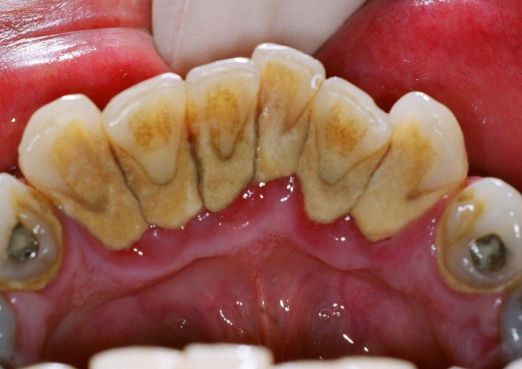

牙龈萎缩主要分为病理性牙龈萎缩和生理性牙龈萎缩两类,病理性牙龈萎缩主要是因为在患者的龈缘部分有牙结石存在,但又长时间的不能得到有效的清理,各种细菌滋生刺激而引发的病理性牙龈萎缩。

牙齿磨合力过大也会造成牙龈萎缩,牙龈底部结石会引发牙龈萎缩等,这些都会引发牙龈萎缩的发生。

牙根处的牙结石